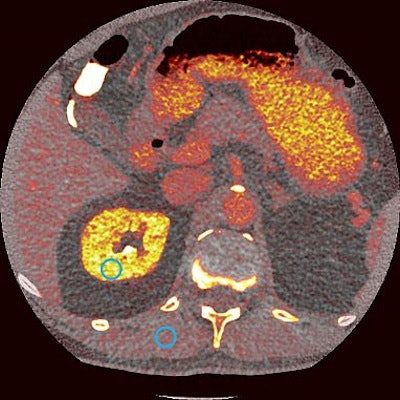

For one, the U.S. Food and Drug Administration (FDA) approved lutetium-177 (Lu-177) prostate-specific membrane antigen radioligand therapy (Pluvicto, Novartis) for the treatment of patients with metastatic prostate cancer.

On the same day, the FDA also approved Novartis' kit (Locametz) for the preparation of the radiotracer gallium-68 (Ga-68) PSMA-11, which is used in PET imaging to identify metastatic prostate cancer tumors.

The approvals mark significant milestones in the emerging field of theranostics -- a term derived from "therapeutics" and "diagnostics" to describe the use of targeted radiopharmaceuticals to both image and treat cancer.

The FDA granted priority review for Lu-177 PSMA-617 in September 2021 based on positive data from the multicenter phase III VISION study. In 800 men with PSMA-positive prostate cancer that had progressed despite standard treatments, 38% showed a reduced risk of death and a 60% reduced risk of progression when treated with Lu-177 PSMA-617.